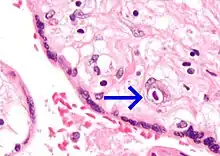

| Micrograph of cytomegalovirus (CMV) infection of the placenta (CMV placentitis), a vertically transmitted infection: The characteristic large nucleus of a CMV-infected cell is seen off-centre at the bottom right of the image, H&E stain. | |